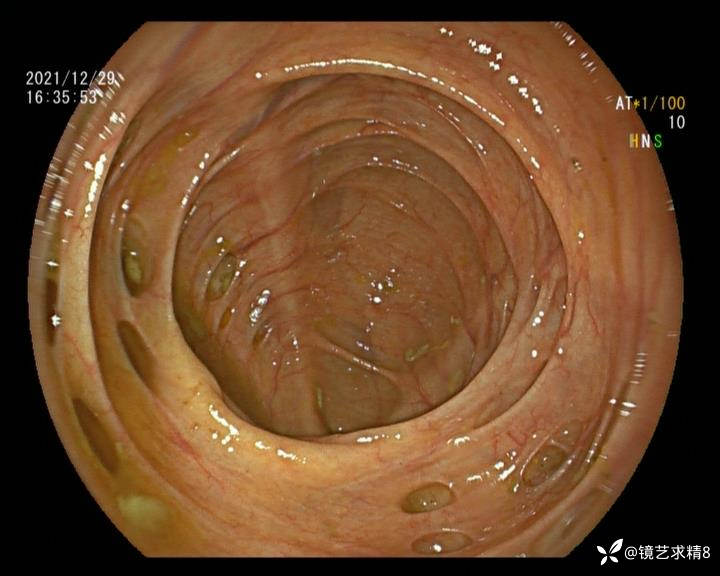

结肠内违建⥤结肠多发憩室☞续

小壮兵爱学习等 2人推荐看到手机存有2年前一个病例仅有的3张图片,因为没有更多的图片就只描述了多发憩室这个内容,没想到浏览量很快上万,很多都和我一样第一次见这么多憩室的结肠,就不得不想要把2年前所有的片子拷贝出来分享。该病例憩室合并外源性因素成为憩室出血的原因。后面附有代表性的全结肠图片。

患者以消化道出血入院,胃镜未见异常,肠镜进入乙状结肠就看到很多憩室,同时还看到肠腔用清肠药后移动下来1枚尖锐的枣核,这么多憩室,这个枣核扎入憩室的机会非常大,推测应该是掉入一坑🕳就算出来还会有很多坑🕳🕳🕳等着,掉入憩室内很容易刺破血管,这可能就是消化道出血的原因,继续前进可以看到有一些憩室内翻,还有一些息肉,问题来了,那么多憩室,犯罪分子是抓住了,它在那些憩室内作过案?到达回盲部后挨个冲洗,但憩室大小又不足以把镜头进入憩室内观察,针对有血块的憩室冲洗后可疑出血的以夹子闭合或套扎,取出枣核,如果有锥形透明帽可能钻入憩室精准电凝效果更好,若内镜下操作失败介入治疗成功率更高,经内镜下治疗后观察未再出血出院。